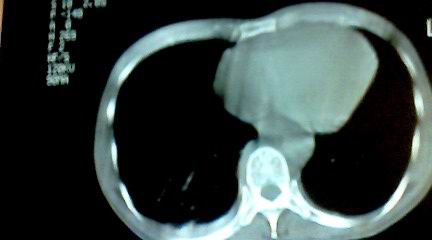

标题: CT25218:请教!胸部CT,胸8椎体骨质破坏,伴周围软组织肿。 [打印本页]

标题: CT25218:请教!胸部CT,胸8椎体骨质破坏,伴周围软组织肿。

患者,女41岁,肢体乏力。

两肺上叶继发性肺结核;胸椎结核并椎旁寒性脓肿形成。

胸椎结核并椎旁寒性脓肿形成。